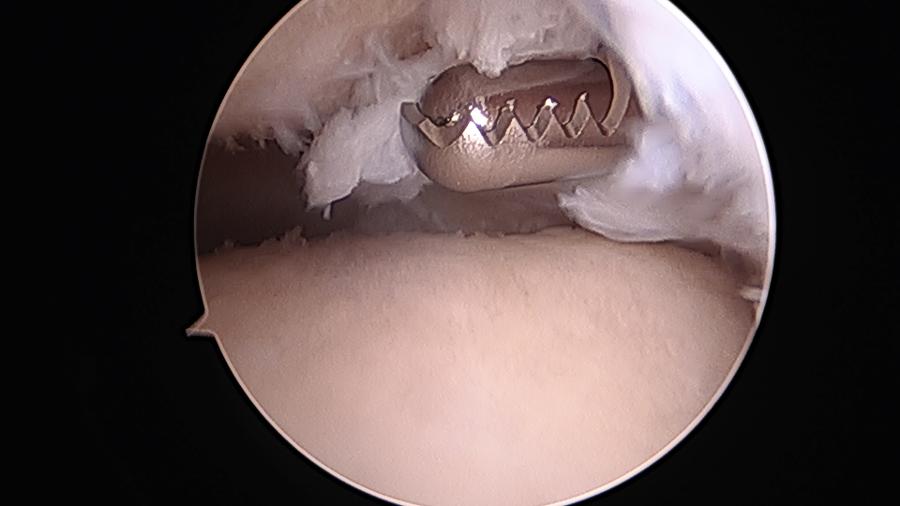

ΑΘΛΗΤΙΚΕΣ ΚΑΚΩΣΕΙΣ:

Αρθροσκόπηση γόνατοςΡήξη μηνίσκουΡήξη χιαστούΑρθροσκόπηση ώμουΡήξη τενοντίου πετάλουΑκρωμιοπλαστικήΑρθροσκόπηση ποδοκνημικήςΑρθροσκόπηση Αγκώνα - Πηχεοκαρπικής

Συγκεκριμένα αναλαμβάνει περιστατικά παθολογίας όπως σκολίωση, αυχενικό σύνδρομο, σπονδυλική στένωση, τενοντίτιδες, αθλητικές κακώσεις, πλατυποδία, άκανθα πτέρνας, οστεοπόρωση κ.α.,χειρουργικές επεμβάσεις όπως διαδερμική χειρουργική, μεταταρσαλγία, βλαισό δάκτυλο, γαμψοδακτυλία, νευρίνωμα Μόρτον, πτώση μεταταρσίων, οστεοαρθρίτιδα, αρθροπλαστική γόνατος, αρθροπλαστική ισχίου, αρθροσκόπηση γόνατος, ρήξη χιαστού, ρήξη μηνίσκου, αρθροσκόπηση ώμου, σύνδρομο καρπιαίου σωλήνα κ.α.